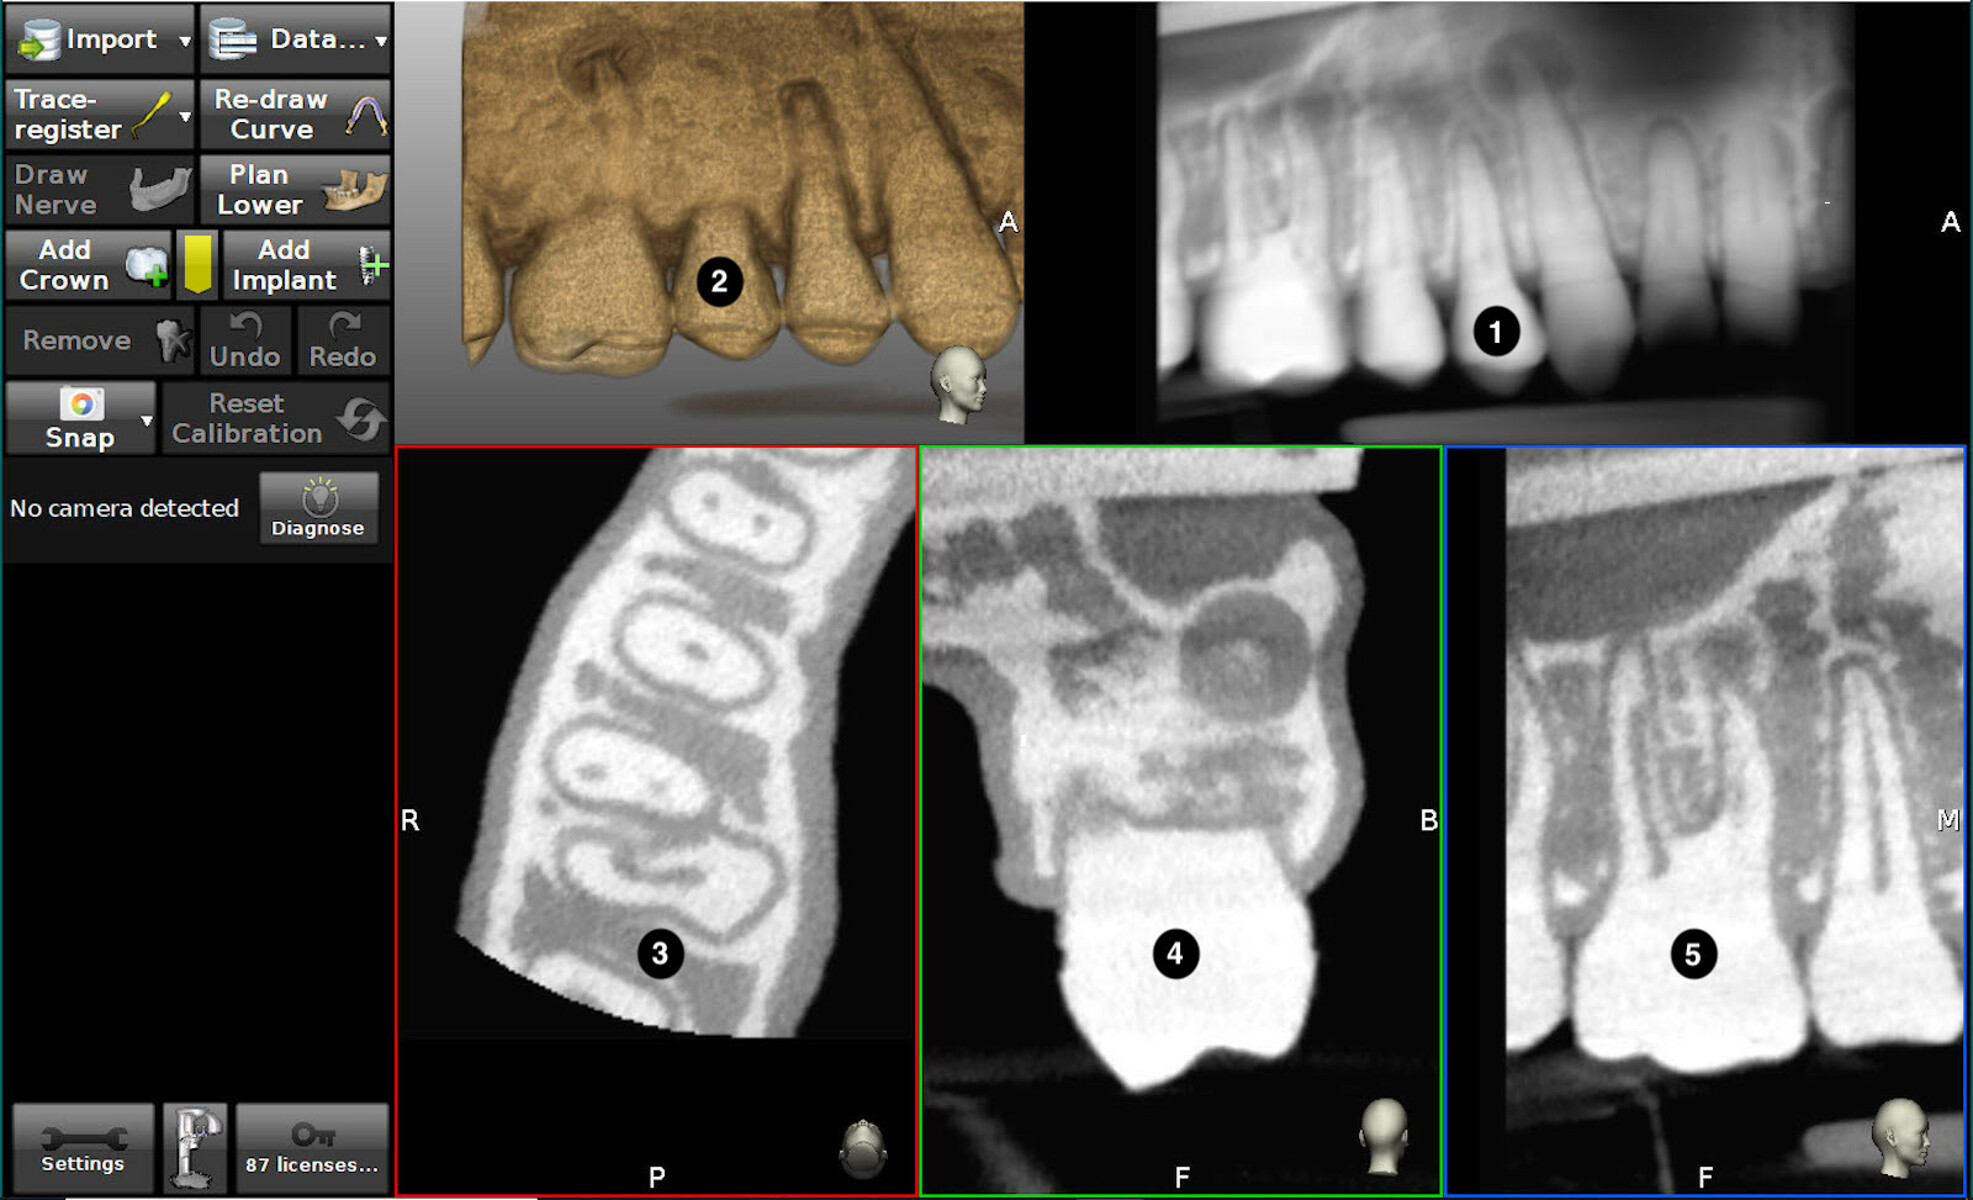

From www.claronav.com

Dynamic Navigation in Endo Hands On ClaroNav Dynamic Navigation System In Endodontics Web inherited from implant dentistry, the dynamic navigation system (dns) is a breakthrough technology for. This scoping review (scr) was conducted to map the existing literature on dynamic. Web the dns demonstrated accuracy and efficiency in performing minimally invasive access cavities, locating calcified canals,. Web learn how dynamic navigation (dn) can guide endodontic procedures such as root canal localization and. Dynamic Navigation System In Endodontics.